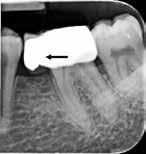

Fig. 2. Tidligere behandlet tand med insufficient eller helt manglende rodfyldning i kanalerne. A. Præmolarer i overkæben med tre insufficiente rodfyldninger og efterfølgende restaurering med stiftopbygning og krone. Desuden første molar uden synlig rodfyldning, men med restaurering, der inddrager pulpakammeret. B. Første molar i overkæben, som kun har synlig rodfyldning i den palatinale kanal. C. Insufficient rodfyldning eller overset rodkanal i første molar i overkæben.

Fig. 2. Previously treated tooth with no or inadequate root filling in canals. A. Maxillary premolars with 3 roots inadequately filled and restored with post and crown. Maxillary first molar with no visible root filling with restoration in pulp chamber and coronal restoration. B. Maxillary first molar with visible root filling only in the palatal canal. C. Inadequate root filling or missed root canal in maxillary first molar.

peroperative faktorer. En af dem er manglende behandling af en rodkanal, enten fordi den ikke blev fundet, eller fordi tandlægen ikke ledte efter den (Fig. 2A-C) (8,9). Det er påvist, at apikal parodontitis forekommer hyppigere i tænder med mindst én ubehandlet eller overset rodkanal (10). Accidentelle perforationer fører ofte til ekstraktion af tanden, men kan almindeligvis undgås med fornuftige endodontiske arbejdsgange (11). Ufuldstændig instrumentering eller forsegling af rodkanalen enten som følge af forkert rodmål eller på grund af fx instrumentfraktur, hyldedannelse eller overinstrumentering af den apikale konstriktion kan føre til, at infektionen persisterer. Rodfile kan frakturere som følge af cyklisk træthedsbrud eller vridningsbelastningsbrud, og incidensraten for brud ligger på 1 % (12). Det sted i tandsættet, der oftest giver anledning til instrumentfraktur, er den apikale del af en mesiofacial rodkanal i en molar (Fig. 3). Kraftig afbøjning af kanalen forøger risikoen for, at filen frakturerer (13). En for kort rodfyldning (> 2 mm fra radiologisk apex) har ligesom overfyldning med guttaperka en nedsat succesrate (14).